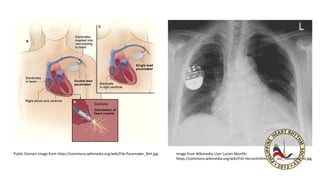

Public Domain image from https://commons.wikimedia.org/wiki/File:Pacemaker_NIH.jpg Image from Wikimedia User Lucien Monfils:

https://commons.wikimedia.org/wiki/File:Herzschrittmacher_auf_Roentgenbild.jpg